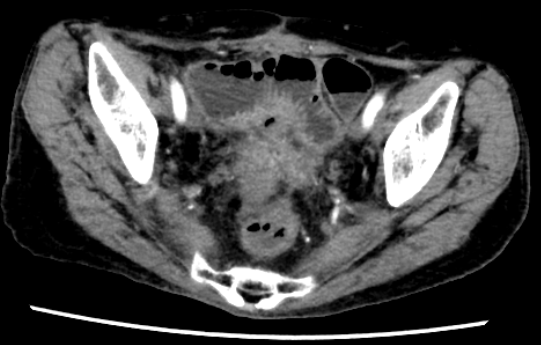

79岁的罗奶奶,20年前进行了卵巢癌根治术,术后1年出现阴道残端复发又进行了盆腔放疗。7个月前复查时PET-CT发现盆腔肿物怀疑为卵巢癌复发,在外院进行了开腹探查,术中见腹腔严重粘连,行小肠部分切除术及回肠造口术。不幸中的万幸,盆腔肿物病理结果为炎性组织,并非肿瘤复发。但罗奶奶并未充分评估身体状况,回肠造口还纳术后出现了严重的切口感染,再使用各级抗生素后又出现了顽固性的腹泻,更不幸的是出现了直肠阴道瘘,粪便改道持续从阴道流出给患者带来了巨大的痛苦。一系列地打击使患者体重从60公斤下降至40公斤,营养状况极差,并且出现多重耐药。

所幸患者家属经他人介绍,了解到了浙江省中医院胃肠外科陈贵平主任团队,随即到省中医院住院治疗。陈主任与患者及家属充分沟通,全面了解患者情况后,立即组织全院的讨论,与各科室专家充分交流后制定周全的治疗方案。患者经过充分的肠内外营养支持,康复锻炼恢复肌肉功能,体重上升了3公斤后,陈主任果断决定进行手术治疗。术中见腹腔内广泛的粘连,尤其是放疗导致的盆腔组织粘连,十分致密。经过陈主任不懈的努力,成功分离出直肠和阴道的瘘口,将瘘口切除后,重新吻合直肠和乙状结肠,并进行回肠预防性的造口。目前罗奶奶已恢复饮食,并且解决了阴道流粪的痛苦。

通过这个案例,我们感悟到放疗对肠道的损伤可以持续多年,化疗结束后20年仍会出现放射性肠炎、肠损伤及肠梗阻;对复杂的肠瘘病人术前营养治疗非常重要围手术期多学科合作还需丰富的处理肠粘连经验手术需分离出足够长度的肠道进行瘘口切除和肠道吻合。